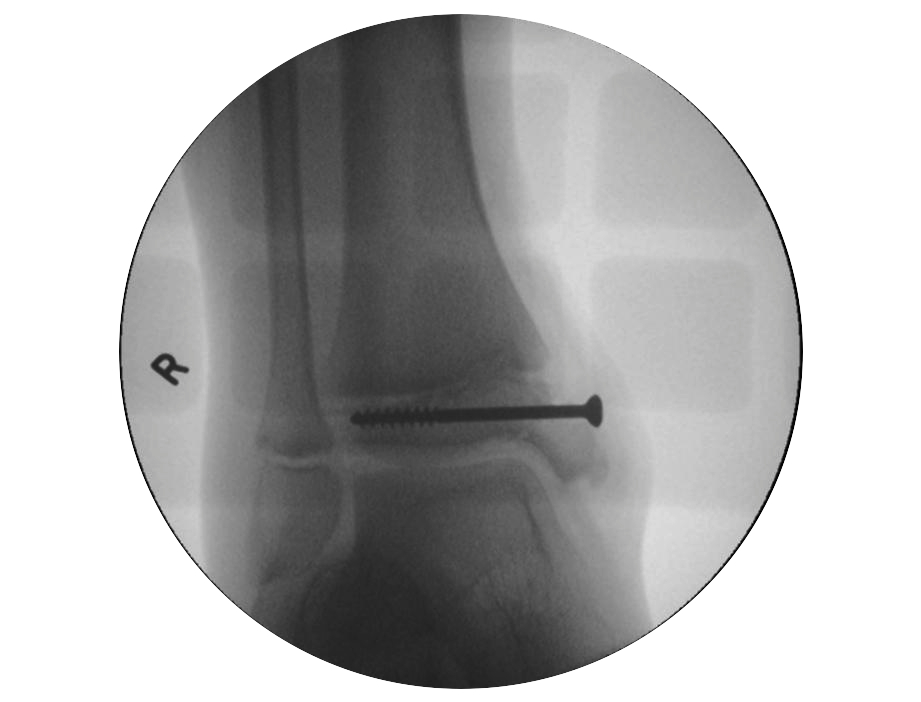

Salter Harris III / Tillaux

Definition

- SHIII of anterolateral distal tibia

- epiphyseal avulsion of AITFL

- supination / ER injury

Management

ORIF

- reduce articular step / prevent physeal bar

- anterolateral incision to reduce

- either anterolateral 4 mm cannulated screw or

- place screw percutaneously from medial side